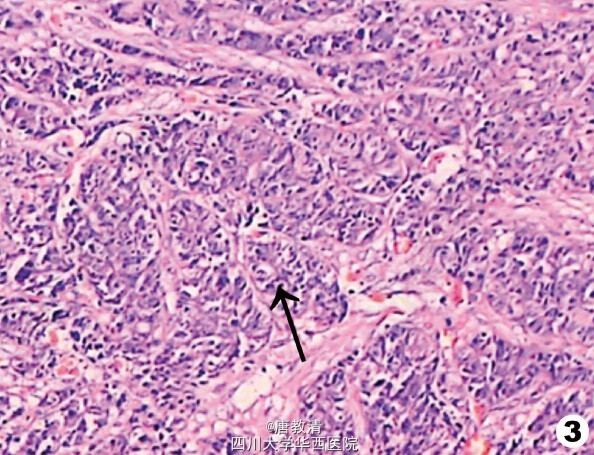

本病诊断主要通过组织活检确认是否继发于内脏肿瘤转移,在组织病理学上,皮肤转移癌一般与原发癌相似,但比原发肿瘤的分化更差,异形性明显。 恶性肿瘤患者发生皮肤转移时,通常已是癌症终末阶段,说明肿瘤已广泛转移。因此笔者认为应采取 综合措施治疗,局部放疗可缩小肿瘤、缓解压迫症状,其效果较好,尤其对仅限于皮肤局部区域的多发病灶及预计生存期较长者可作为治疗首选。